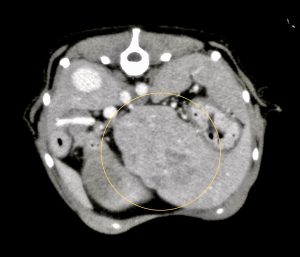

今回治療させていただいたワンちゃんは、数ヶ月前から肝臓(尾状葉乳頭突起)の腫れを指摘されており、CT検査で尾状葉乳頭突起に4センチ大の腫瘤性病変と胃の圧迫、重度の胆嚢拡張を認めました。肝臓腫瘍の初期はほとんど症状がなく(稀に低血糖)、腫瘍が大きくなることで他の臓器を圧迫して症状が出ることが多い印象です。

黄線:肝臓腫瘤

赤矢印:圧迫された胃